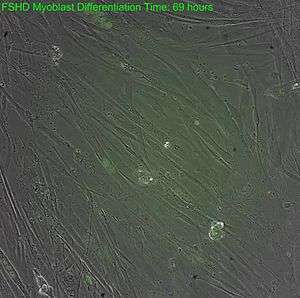

| Facioscapulohumeral muscular dystrophy | 158900 | DUX4 |  Timelapse expression of DUX4 protein in FSHD cells Facioscapulohumeral muscular dystrophy (FSHD) initially affects the muscles of the face, shoulders, and upper arms with progressive weakness.[19] Symptoms usually develop in early adulthood (late teens); affected individuals become severely disabled. The pattern of inheritance is autosomal dominant, though a number of spontaneous mutations occur. Two defects are needed for FSHD, which for the first time provides a unifying theory for the underlying genetics of FSHD.[9][20] FSHD occurs both in males and females.[21] |